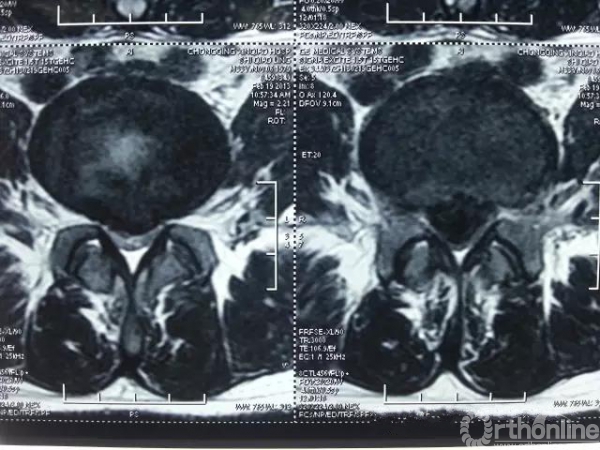

2.腰椎间盘突出症融合手术

复发率只有7%哦!

腰椎间盘髓核摘除术还是腰椎椎间盘突出症手术治疗的金标准。(尽管经皮内镜椎间盘髓核摘除术(PELD)或显微椎间盘髓核摘术还有争论。)

腰椎间盘突出症融合手术适应证:伴腰椎不稳;伴腰椎管狭窄;伴终板炎II级;巨大型椎间盘突出症(马尾综合征);术后复发;惧怕复发率为7%的患者等。